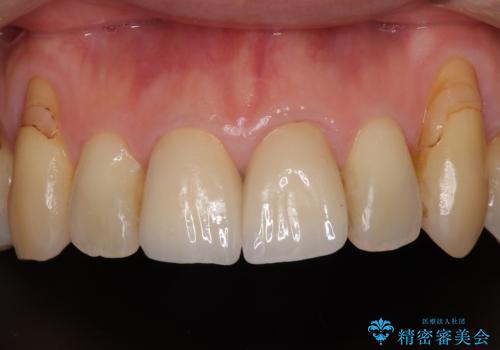

しみる前歯のセラミック治療 周辺も同時に治療して調和の取れた前歯に